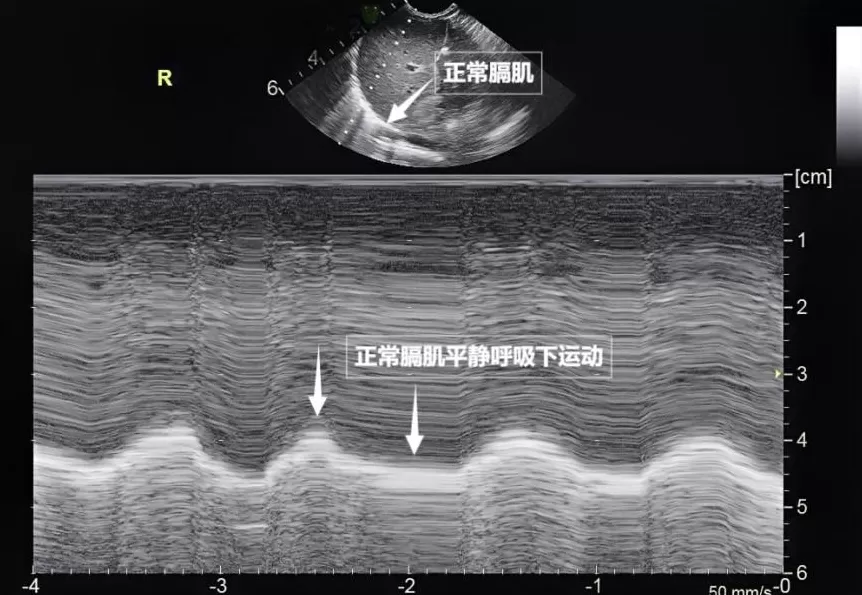

第三景:" 呼吸的动力泵 " 的协同作战——呼吸肌肉

呼吸看似简单,实则是多组肌肉精密配合的 " 团体操 "。肺部超声不仅能观察肺的形态,更能通过实时动态影像," 捕捉 " 这些呼吸肌的活动状态,为评估呼吸功能提供独特视角。膈肌是呼吸肌的 " 总指挥 ",位于胸腔与腹腔之间。平静呼吸时,膈肌收缩下沉,胸腔容积扩大,空气自然吸入;舒张时,膈肌回升,肺部弹性回缩完成呼气。超声下可见膈肌呈光滑弧形,随呼吸规律上下移动(见下图)。肋间外肌则是 " 肋间隙的升降机 ",收缩时上提肋骨,扩大胸腔前后径,辅助吸气。这对 " 黄金搭档 " 承担了日常呼吸 70% 以上的工作量,是维持呼吸的 " 主力军 "。

图为正常膈肌超声表现

肺部超声这位 " 侦察兵 ",通过观察肌肉激活顺序、测量膈肌厚度与移动度、捕捉肌肉矛盾运动,动态评估呼吸肌肉的变化,早期发现呼吸系统 " 超负荷运转 " 的信号,为医生调整治疗方案提供精准依据。